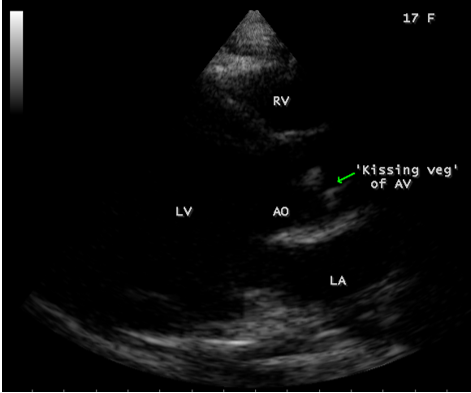

A 17-year-old female was brought to the emergency room with a history of sudden onset of breathlessness. Her pulse rate was 87 bpm and blood pressure 110/60 mmHg. She had a history of rheumatic fever during childhood, an episode of febrile illness for 10 days and taken antibiotic treatment recently. Blood chemistry revealed normal and blood cultures were negative. ECG revealed normal as shown in Figure 1 and X-ray chest revealed dilated LV (left ventricle) as in Figure 2. Physical examination revealed grade 3/6 early diastolic murmur over left mid sternal border, basal crackles over lung fields and no peripheral signs of wide pulse pressure. Transthoracic echocardiography revealed vegetations on anterior and posterior leaflets of aortic valve as in Figure 3 and Figure 4, with a “kissing-type “as in Figures 5, 6 and 8. The aortic valve was bicuspid with an attached vegetation as in Figure 9 and it was severely regurgitant as in Figure 10 and Figure 11. The left ventricle is dilated as in Figure 12 with moderate LV dysfunction as in Figure 13. The thoracic aorta was prominent as in Figure 14 with a ‘holodiastolic flow reversal’ as in Figure 15. The patient was treated with digoxin (0.25 mg, half daily), diuretics (Injection. Furosemide 20 mg IV twice daily), ACE inhibitors (tablet. Enalapril 2.5 mg twice daily) along with 2 weeks course of intravenous (IV) cefotaxime (1g) and amickacin (500mg) twice daily and advised aortic valve replacement at the earliest with lifelong penicillin prophylaxis and continuation of antibiotics for 6 weeks since the vegetations remain stable after 2 weeks of treatment, but without any embolic episodes.

Figure 5: Parasternal long axis view showing the “ kissing-type” of vegetations (arrow) on the aortic valve in a 17-year old female.

Figure 6: Parasternal long axis view showing the “ kissing-type” of vegetations (arrows) on the aortic valve in a 17-year old female- large view.

masses with atypical location. Transthoracic echocardiography detects 70% of vegetations > 6 mm and 25% of vegetation < 5>Figures 3 to 9. When endocarditis involves the aortic leaflets, the resultant acute, severe regurgitation as shown in Figures 10, 11 and 15, may often causes dilated left ventricle as in Figure 12 and a prominent aorta as in Figure 14. Secondary infection of mitral valve is a possible finding in primary aortic valve endocarditis. Large aortic valve vegetations (> 6 mm) prolapse into the left ventricular outflow tract and “kiss” the ventricular surface of the anterior mitral leaflet with the development of a vegetation [27],[28],[29]. The left ventricular outflow tract endocarditis may represent the initial site of infection with a possibility to spread by contiguity to both left-sided valves, the mitral and aortic [30], causes the “mitral-kissing vegetation” with a higher prevalence of embolic events [31].